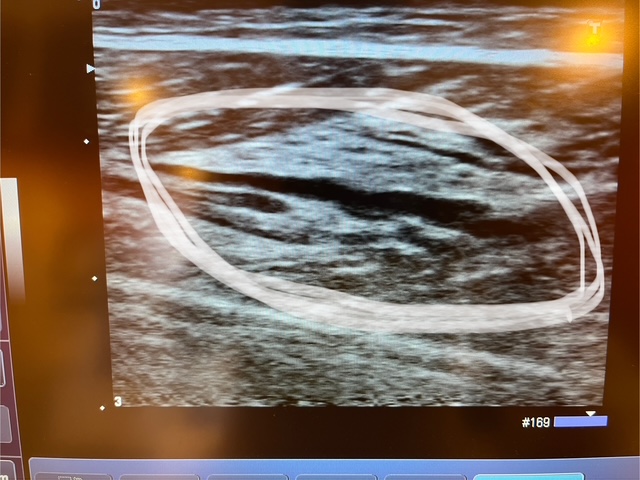

エコーを撮ってみると、

このように筋肉が裂けているような感じになっています。

完全にふくらはぎの肉離れ。。